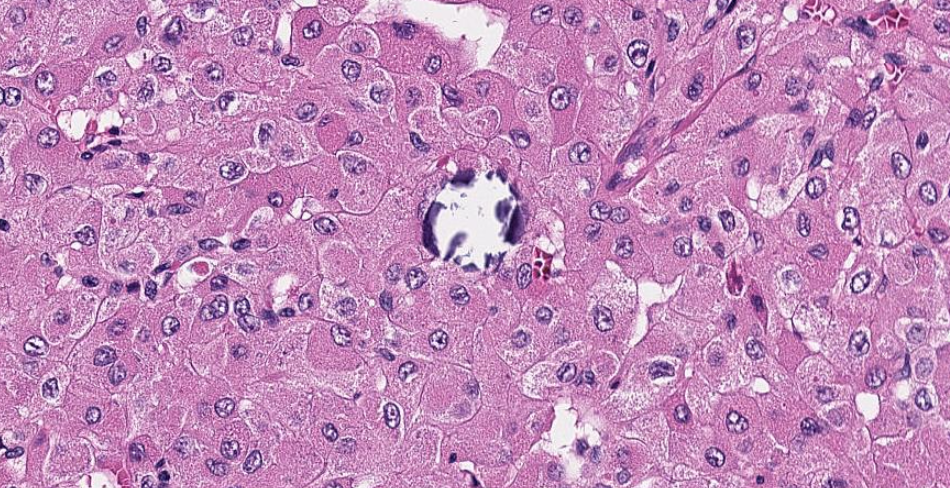

DIAGNÓSTICO: CARCINOMA DE CÉLULAS RENAIS SÓLIDO E CÍSTICO EOSINOFÍLICO

Macroscopicamente são tumores circunscritos, mas sem uma cápsula bem formada na periferia. O revestimento epitelial dos cistos tem aspecto em hobnail e as trabéculas do cisto podem variar em espessura. As células nas áreas sólidas do tumor é semelhante às vistas nas trabéculas entre os cistos, mostrando crescimento difuso, acinar compacto ou compacto em ninhos. Agregados dispersos de histiócitos espumosos e linfócitos são frequentemente encontrados. As células normalmente mostram citoplasma eosinofílico volumoso, com grânulos citoplasmáticos grosseiros, basofílicos a púrpura prontamente identificáveis , que representa uma característica morfológica muito útil; esses grânulos correspondem a agr egados de retículo endoplasmático rugoso, observados na microscopia eletrônica. Os núcleos são redondos a ovais com nucléolos focalmente proeminentes, equivalente ao WHO / ISUP grau 2 ou 3. Outras características menos comuns ou menos específicas também podem estar presentes, incluindo crescimento papilar focal, áreas focais de “células claras”, bem como crescimento insular ou tubular focal e aglomerados de células multinucleadas. A vacuolização intracitoplasmática, microvesicular ou macrovesicular, também é comum e corpos de psamoma podem ser encontrados em cerca de metade dos casos. A imuno-histoquimica desses tumores mostra alguma variabilidade, embora citoqueratina 20, PAX 8 e vimentina sejam geralmente positivos, CD10, racemase e antígeno de membrana epitelial podem ser ambíguos, enquanto citoqueratina 7 e CD117 são geralmente ne gativos.